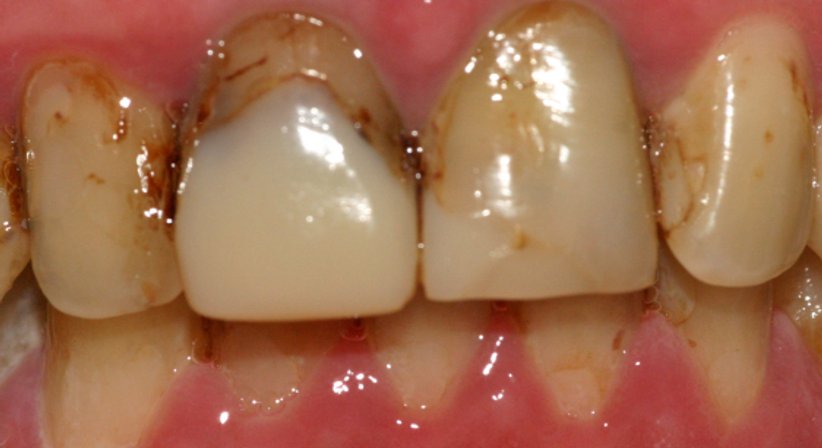

Es gibt unterschiedliche Arten von Zahnkronen, darunter Verblendmetallkronen und Keramikkronen. Zahnkronen aus Keramik haben den Vorteil, dass sie metallfrei sind und als solche mit einer ausgezeichneten Verträglichkeit einhergehen. Dank heutiger Hochleistungskeramiken können Kronen angefertigt werden, welche mit einer ähnlichen Stabilität einhergehen wie Kronen aus Metall, gleichzeitig ist eine Zahnkrone aus Keramik hinsichtlich ihrer Optik weitaus natürlicher und ästhetischer als eine Krone aus Metall (Verblendmetallkronen können unter Umständen im Zahnhalsbereich durch die Schleimhaut schimmern oder im Fall von Zahnfleischrückgang durch einen dunklen Rand sichtbar werden.).

- wenn Zähne stark durch Karies zerstört sind.

- nach einer Wurzelbehandlung.

- nach einem Kronenbruch.